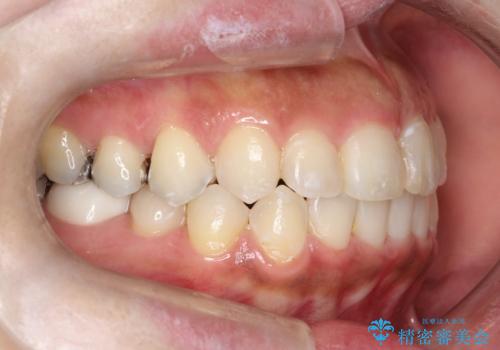

前歯のガタつきをマウスピース矯正で改善! 驚きの効果を体験しよう

- 前歯のガタツキが気になると来院されました。

マウスピース矯正治療を選択しました。

奥歯の噛み合わせは綺麗に噛んでいたため、前歯の叢生(でこぼこ)に集中して治療するように計画しました。

奥歯の噛み合わせは整っていたため、前歯の並びを美しく修正することに専念できました。

前歯のガタツキを改善する治療法として、マウスピース矯正が適していることが多いです。

マウスピース矯正は、金属製のブラケットやワイヤーを使用せずに、透明なマウスピースを装着して歯を移動させる方法です。そのため、目立たず、痛みも少ないです。